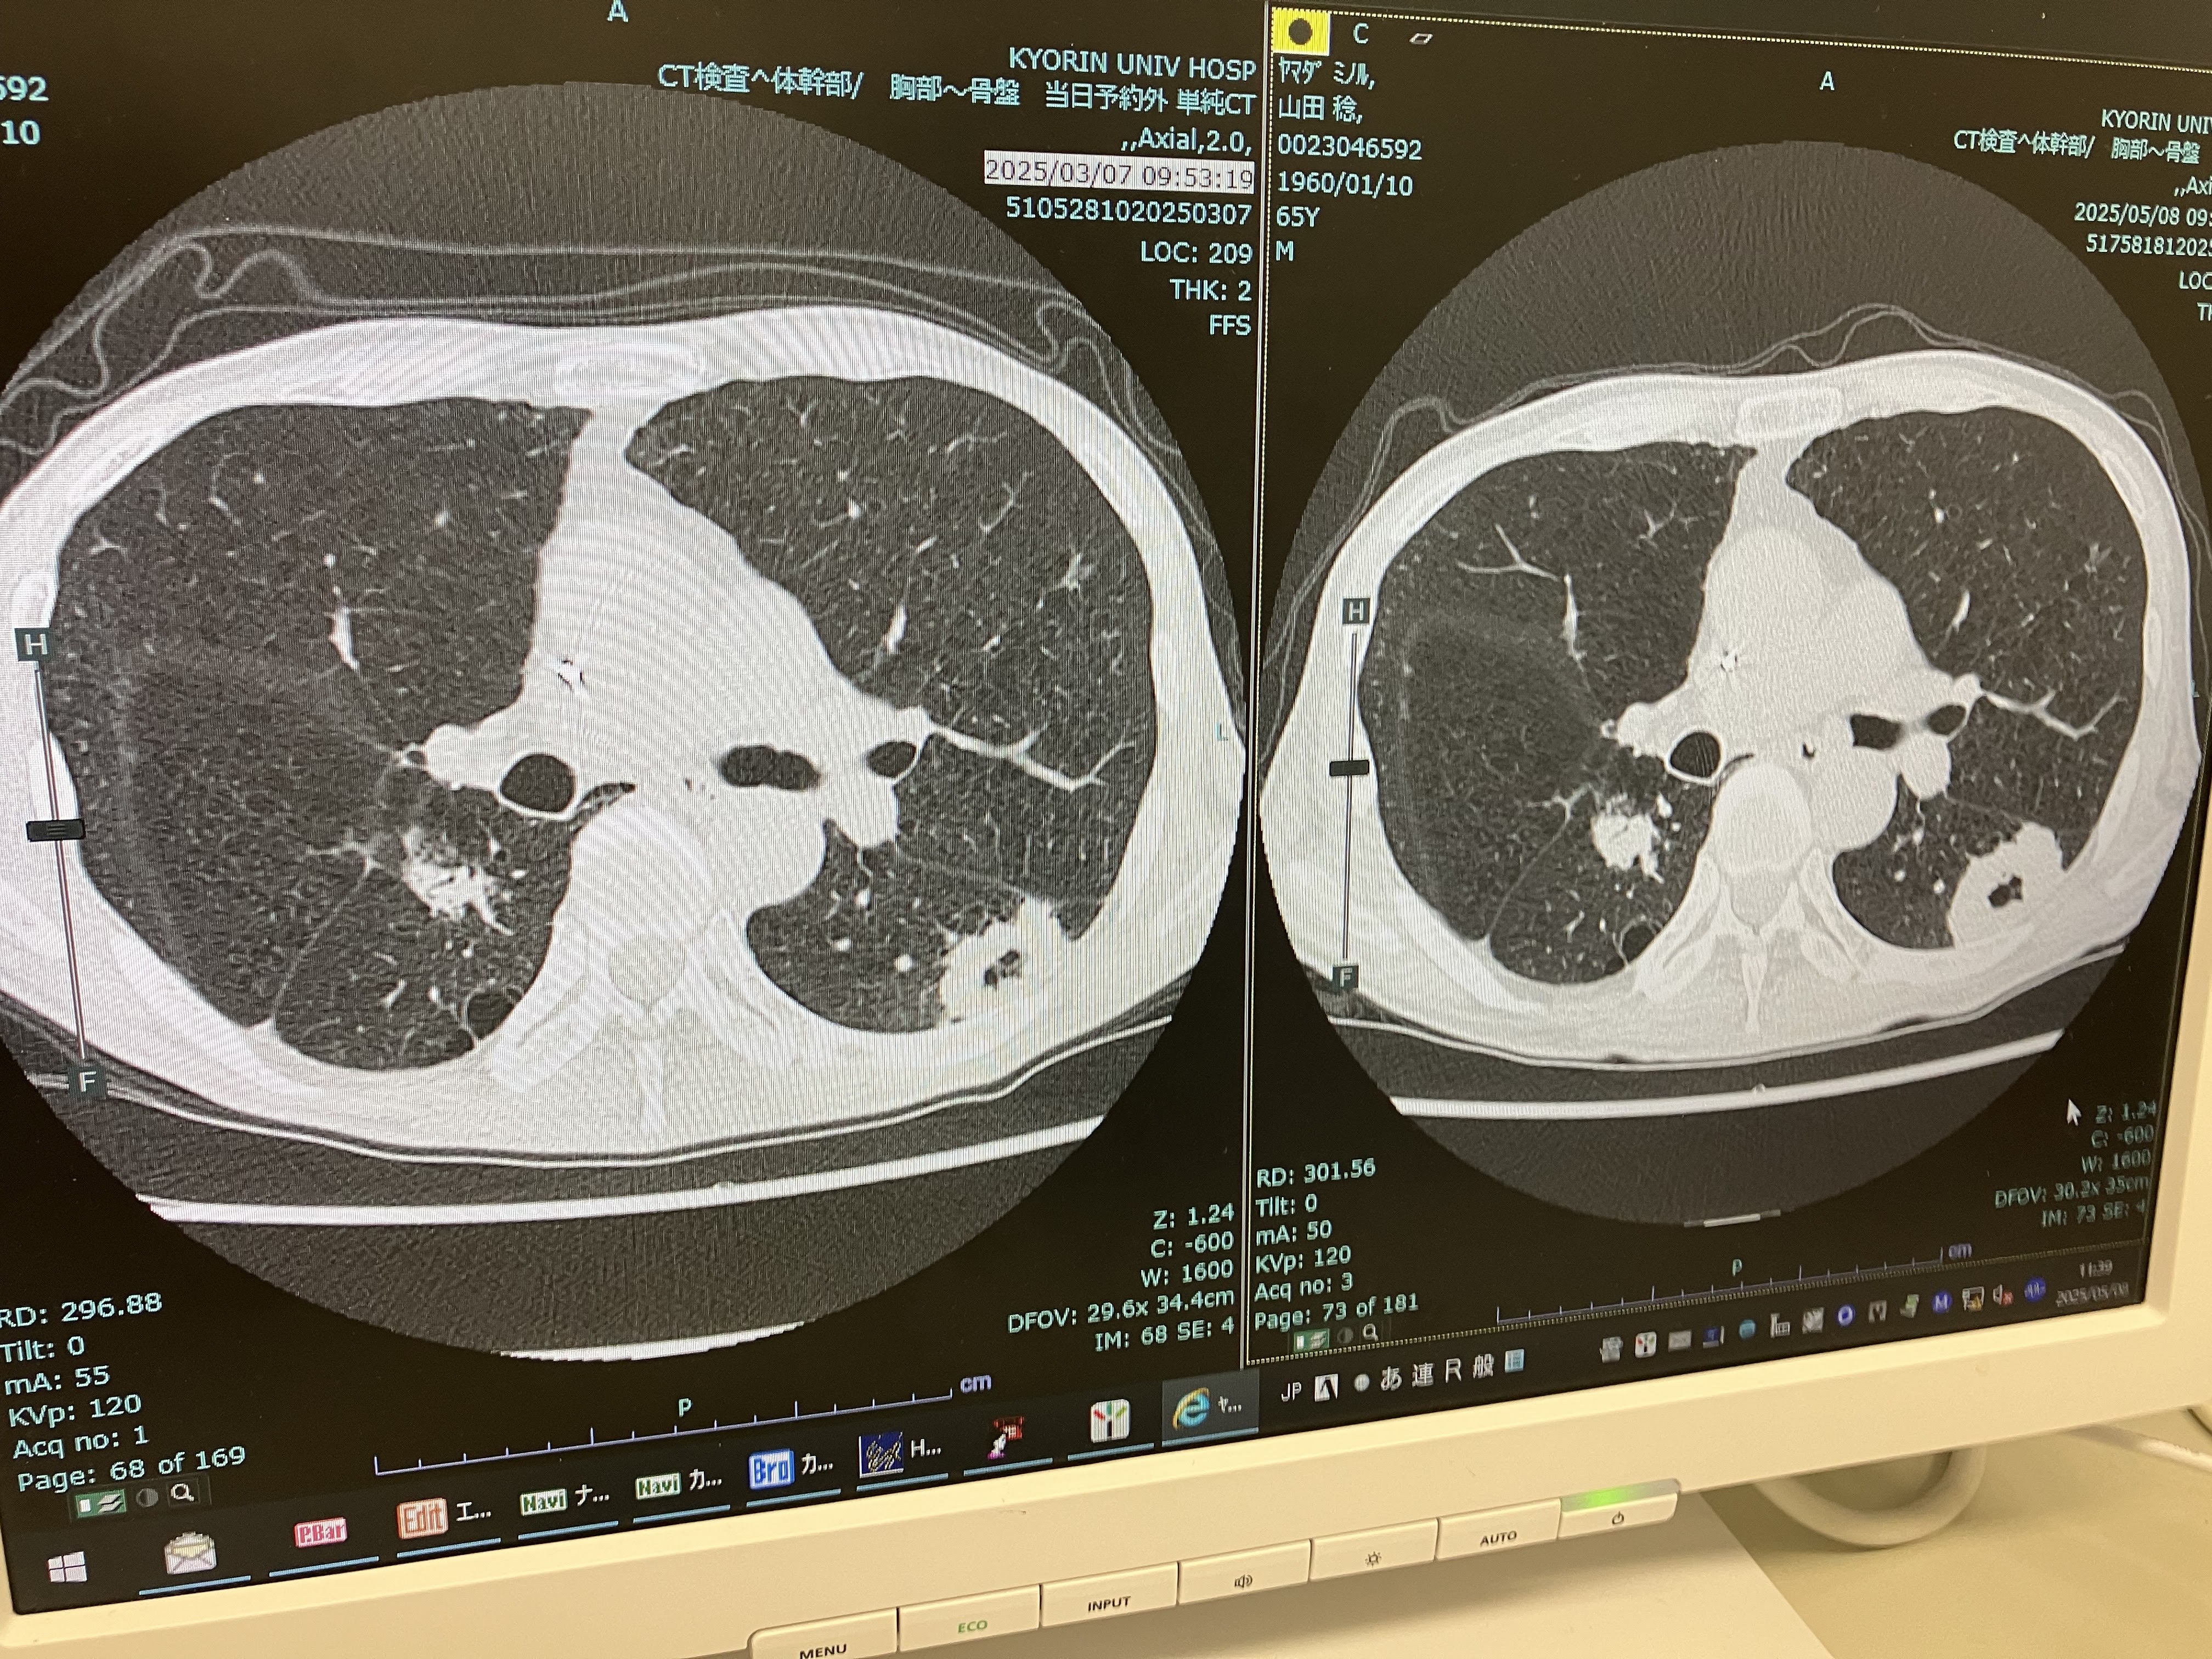

大幅な縮小を期待した板だけに残念だったが、進行を食い止めている点は評価したい。

地道に一歩ずつ治していこう。